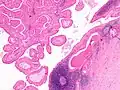

The appearance of this tumor under the microscope is unique. There are cystic spaces surrounded by two uniform rows of oncocytes, which are epithelial cells with abundant, granular, eosinophilic cytoplasm.[7] The cystic spaces have epithelium referred to as papillary infoldings that protrude into them. Additionally, the epithelium has lymphoid stroma with germinal center formation.

Low magnification micrograph of a Warthin tumor arising from the parotid gland.

Histopathology of Warthin tumor in the parotid gland. H&E stain.